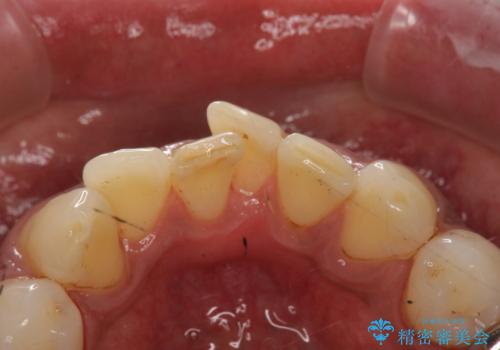

タバコによるヤニをPMTC(歯科医院での専門的クリーニング)で除去。

歯ブラシでは、除去できない着色、汚れが落ち歯の表面もツルツルになって気持ちがいいと喜んでいただけました。